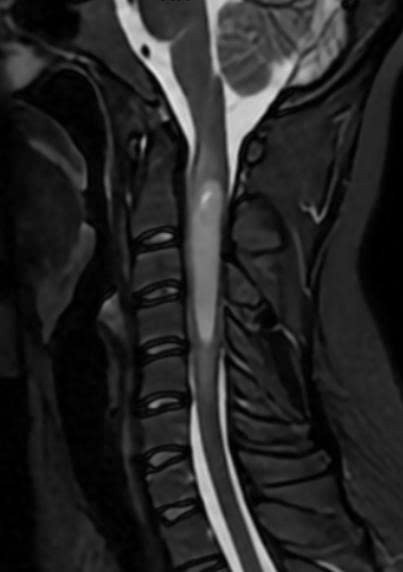

Để chiến thắng trong cuộc chiến bảo vệ tủy sống, lòng dũng cảm và đôi tay tài hoa là chưa đủ. Điểm tựa vững chắc nhất cho ê-kíp phẫu thuật chính là việc làm chủ và triển khai đồng bộ những hệ thống thiết bị y khoa tối tân nhất hiện nay. Ba mục tiêu sống còn được đặt ra: lấy được tối đa khối u, không làm tổn thương tủy lành, và bảo toàn tuyệt đối chức năng thần kinh.

Việc đầu tiên, hệ thống kính hiển vi phẫu thuật hiện đại được huy động để phóng đại phẫu trường. Đặc biệt, công nghệ huỳnh quang đã được ứng dụng để phát quang khối u. Kỹ thuật này đóng vai trò như một chiếc "radar" soi sáng trong đêm, giúp phẫu thuật viên nhận diện rõ ràng ranh giới giữa tổ chức u bệnh lý và phần tủy sống lành lặn, đảm bảo việc cắt bỏ diễn ra chính xác tuyệt đối.

Song song đó, hệ thống theo dõi điện sinh lý thần kinh liên tục trong mổ (IONM) hoạt động theo thời gian thực. Bất kỳ một thao tác nào có nguy cơ làm suy giảm chức năng dẫn truyền thần kinh đều sẽ được hệ thống cảnh báo ngay lập tức. Đây là "tấm khiên" đảm bảo bệnh nhân không thức dậy trong tình trạng tồi tệ hơn trước khi lên bàn mổ.

Cuối cùng, để loại bỏ khối u mà không gây co kéo, dao hút u siêu âm (CUSA) được sử dụng. Bằng sóng siêu âm, tổ chức u bị đánh dập và hút ra ngoài một cách êm ái, giảm thiểu tối đa tác động vật lý lên tủy.